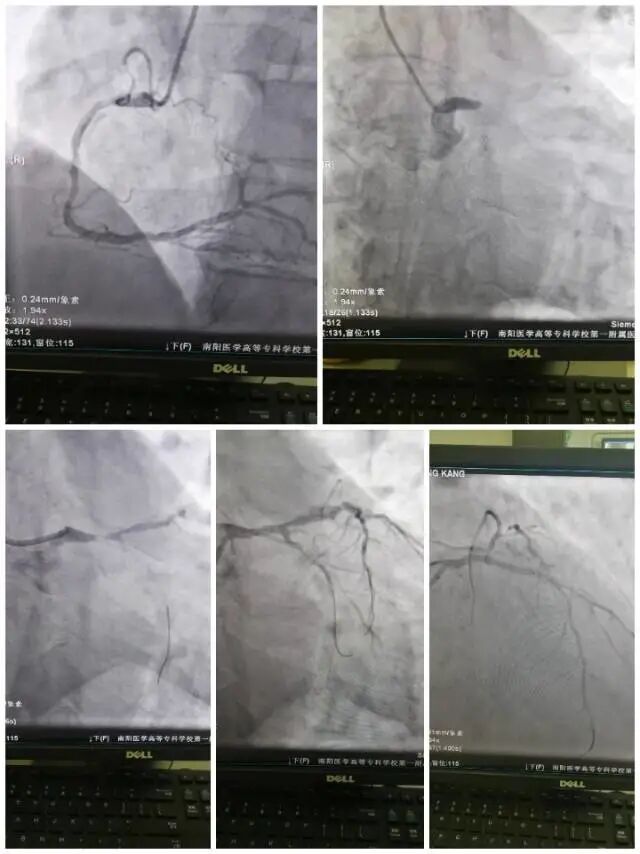

2021年10月1日,国庆长假首日,大家正沉浸在欢庆国庆的轻松、喜悦气氛中,南阳医专一附院冠心病监护病房突然接收一位急性心肌梗死患者,患者为58岁中年男性,持续性胸痛7小时入院,诊断急性心肌梗死,心源性休克,院长助理、科主任张鸥主任医师及科室同仁立即放弃休假,紧急就位,急诊冠脉造影检查显示患者冠脉左主干急性完全闭塞,病情凶险,张鸥主任医师沉着冷静,立即行急诊PTCA及支架植入术,左主干及回旋支、前降支血流顺利恢复正常。

患者冠脉左主干完全闭塞7小时,心肌严重受损,术后出现血压、血氧下降,心源性休克,患者急需应用心脏辅助设备支持,但患者生活和经济负担重,子女和爱人需要患者照顾,为家庭顶梁柱,亲戚无法提供更多经济支持。经济条件受限,患者家属拒绝应用ECMO,而我院唯一一台IABP(主动脉球囊反搏)设备正在应用中,张鸥主任医师、郭胜副主任医师再三讨论,考虑患者病情危重,情况特殊,在患者医疗费用不能到位情况下,要先治病救人,挽救患者生命,挽救一个家庭的希望!患者病情不容耽搁,副院长紧急协调,向兄弟医院求助,南阳医专附属油田总医院积极提供设备援助,我院救护车星夜出发,顺利运回IABP设备,张鸥副院长坐镇指挥,郭胜副主任医师,汤有为主治医师及朱玉果住院医生连夜为患者顺利植入IABP(主动脉球囊反搏)。